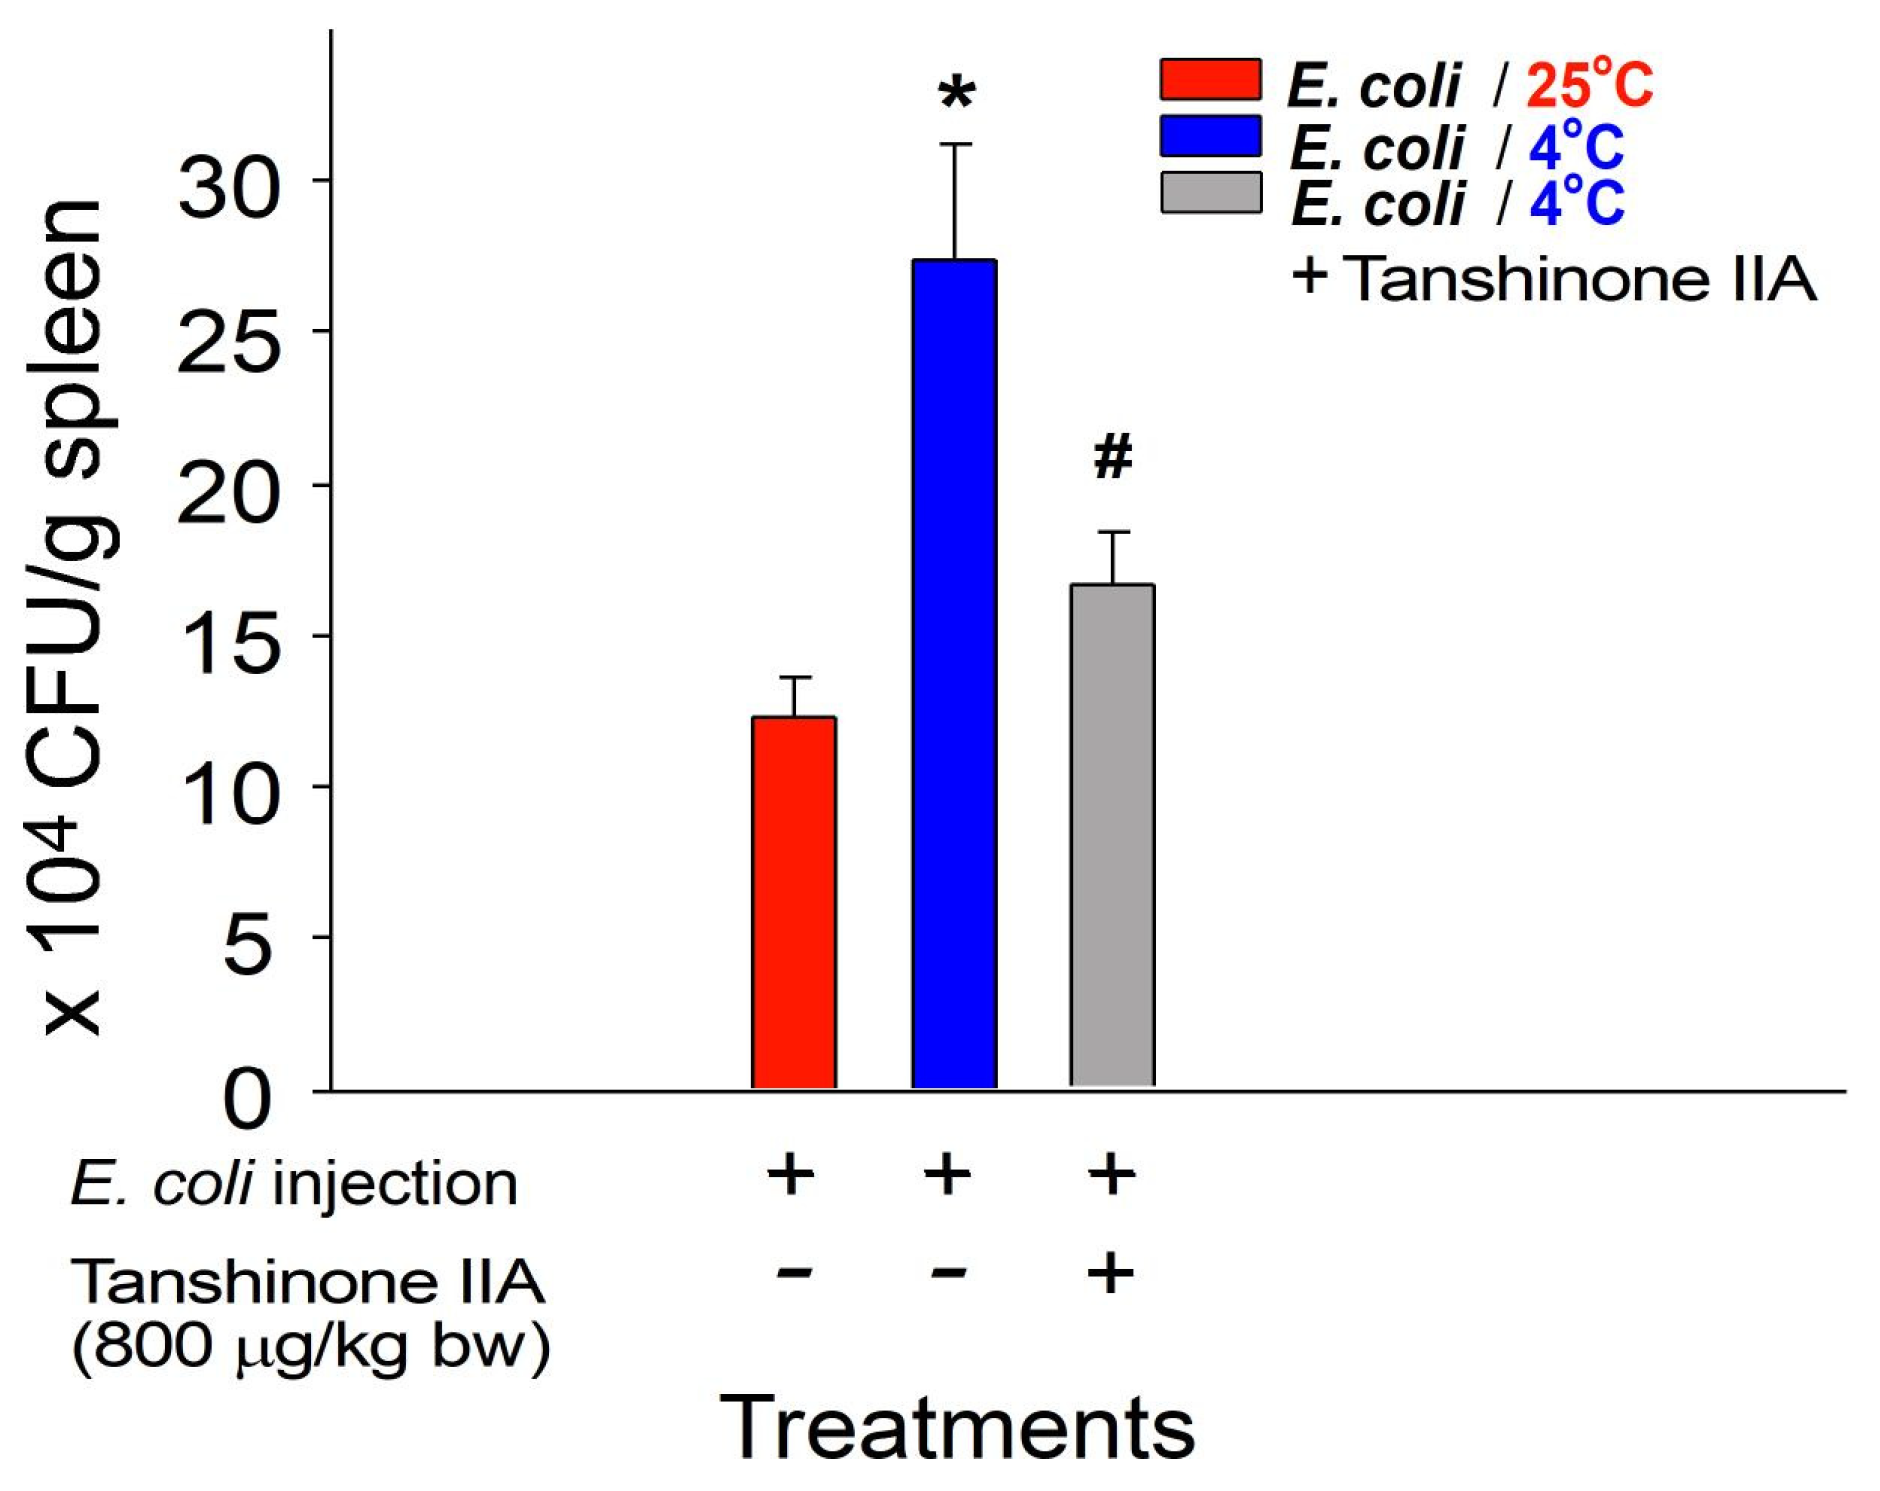

2.2. Reversal of Cold-Induced Immunosuppression in Mice through Treatment with a S. miltiorrhiza Root Component Tanshinone IIA

4.4. Analysis of Bacterial Clearance in the Cold Exposure Mouse Model